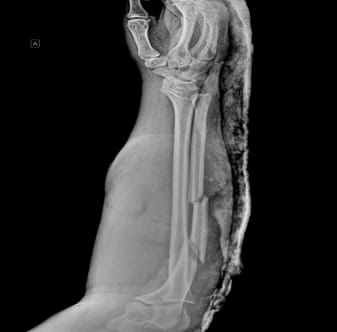

Пациент с тяжелой травмой предплечья обширным дефектом мягких тканей и переломом локтевой кости попал в ВГКБ №2 им. К.В. Федяевского.

Вначале доктора хирургически обработали рану раны с пластикой местными тканями и установили аппарат КСВП (для быстрой чрезкостной фиксации переломов трубчатых костей) на локтевую кость предплечья.

Через две недели провели кожную пластику, где использовали расцепление кожного лоскута. Такую процедуру применят для заживления обширных ран.